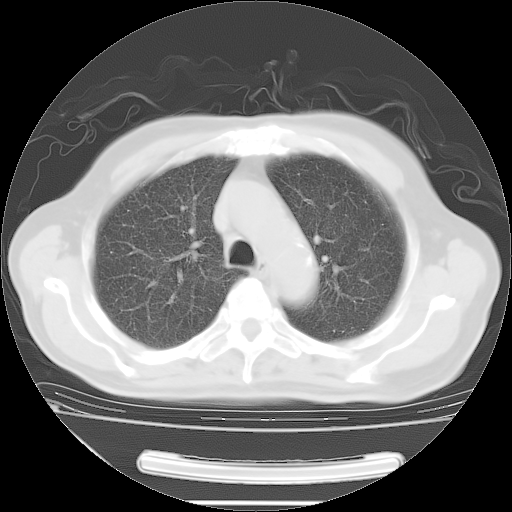

胸腹部CT,诊断意见:左上肺叶钙化灶、左侧胸膜局限性增厚并钙化、胆囊炎。描述部分肺组织呈磨玻璃样改变。

今天复查肺部CT,发现双肺广泛磨玻璃样改变。所以我把3月19日和5月9日相隔50天的肺部CT上传。请大家会诊。

2009年3月19日肺部CT片。

2009年3月19日肺部CT

大致读了系列胸部CT:纵隔窗无明显异常,肺窗:从4、27至今:主要是双肺中下野外带可见毛玻璃样改变,目前处于急性肺泡炎阶段,至于原因考虑1、结替组织或胶原血管性疾病所致?2、恶性疾病如恶组在肺部所致的表现或细支气管肺泡癌?3、药物或其它原因如肺蛋白沉着症所致肺泡炎目前不太可能?总之,明天就去请我院的呼吸科、感染科、血液科和临免专家会诊哈。